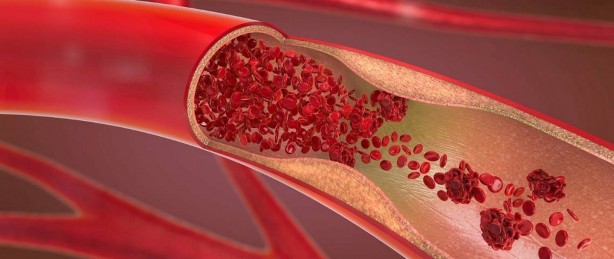

Zayıf kan dolaşımı, damarların elastikiyetini ve tonunu kaybetmesinin sonucu ortaya çıkar, bu da kan dolaşımını yavaşlatır ve zorlaştırır. Bu nedenle, özellikle alt ekstremitelerde zayıf dolaşıma bağlı rahatsızlıklar görülür. Kanın vücudun alt kısmında daha fazla yol alması gerekir ve yerçekimine karşı kalbin daha kuvvetli çalışması gerekir. İlk belirti, çoğunlukla ayak bileği seviyesinde bir ödemin ortaya çıkmasıdır. Şişlik günün sonunda belirgindir ve geceleri bacaklar yukarı kaldırılırsa sabahları kaybolur. Bu şişlik ya çok belirgindir ve şüpheye yer bırakmaz ya da çok daha gizlidir. Bunu, baldırın etrafındaki çorapların bıraktığı dairesel işaretten anlayabilirsiniz.

Bacak bacak üstüne atmaktan kaçının. Bu, adeta bir refleks haline gelen bir durumdur. Bacak bacak üstüne atmak vücuttaki kanın düzgün dolaşımını etkileyebilir. Bu pozisyon bacaklarda basınç oluşturarak kan dolaşımını bloke eder.

Doğru ayakkabıyı giyin. Kan dolaşımı genellikle uygun olmayan ayakkabılar nedeniyle yavaşlar. Daima ayağı, bileği veya baldırı sıkıştırmayan rahat ayakkabılar seçin. Günlük olarak, bacaklardaki baskıyı artıran ve kan dolaşımının düzgün bir şekilde gerçekleşmesini engelleyen yüksek topuklu ayakkabılardan uzak durun. Tersine, çok düz olan ayakkabılardan da kaçının. İdeali 2 ila 3,5 santimetre küçük topuklu ayakkabılardır. Çok dar giysilerden kaçının. Çok dar giysier kan dolaşımı için kötüdür. Çok dar pantolonların neden olduğu sıkıştırma, kan dolaşımını yavaşlatır. Ayrıca vücudu saran çorap, külot veya taytlardan kaçının.

Sarımsak Sarımsak kan akışkanlığı üzerinde etkili olan ajoene maddesini içerir. Kan dolaşımını iyileştirmenin yanı sıra tansiyonu düşürücü etkisi vardır ve böylece yüksek tansiyonla savaşır ve pıhtı oluşumunu önler. Günde bir diş çiğ sarımsak yemek yeterlidir. Kükürt bileşiklerini harekete geçirmek için taze sarımsağı ezerek tüketin.